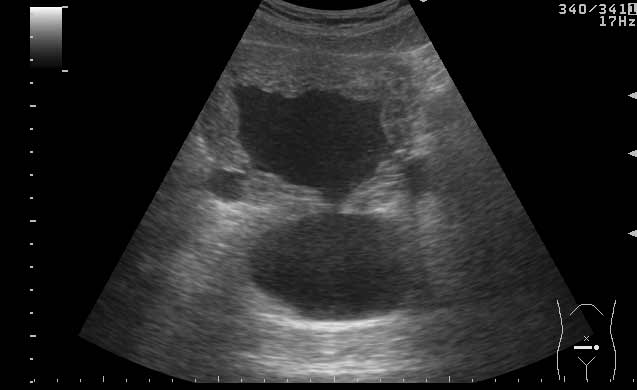

УЗИ мочевого пузыря у пожилого мужчины выявлены следующие изменения.

Signs of chronic urinary retention; evident thickening of the urinary bladder mucosa; large diverticulas. Residual volume evlaluation required; full prostatic assessment is recommended.

But really there are two ones on these pictures.

неравномерное утолщение стенок мочевого пузыря,признаки застоя в мочевом пузыре,расширенные дистальные отделы мочеточников,на первом снимке-дивертикул?слева,уввеличенная отечная простата

Все верно, за исключением того что простаты на картинках нет. Здорово, что Вы заметили расширение мочеточников. Есть также воздух в МП после цистоскопии.